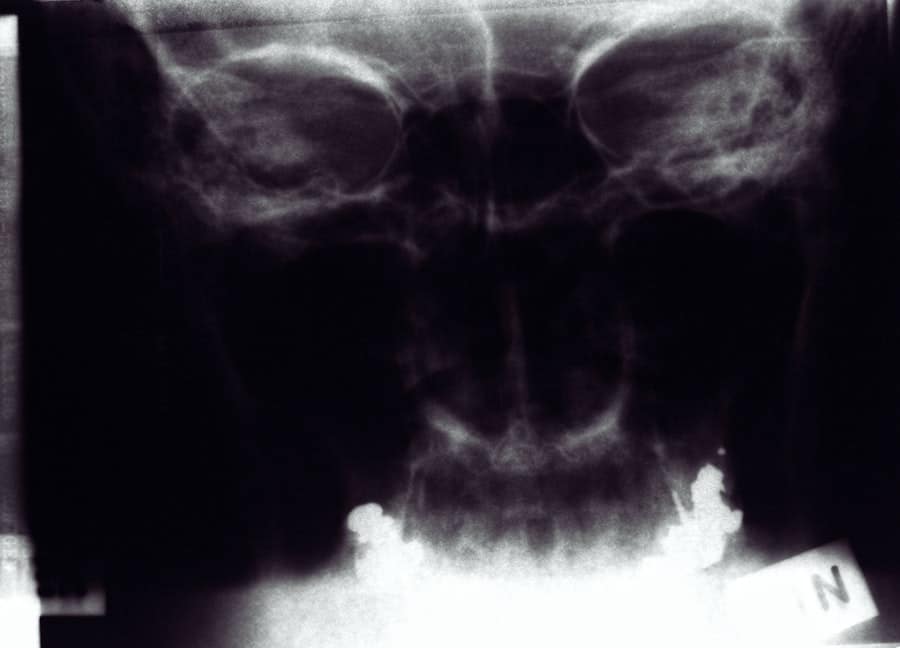

What is rhinoplasty?

Rhinoplasty, commonly known as a nose job, is a surgical procedure to reshape or resize the nose for cosmetic or functional purposes.